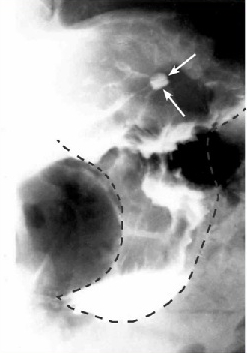

צילום קיבה בעזרת חומר ניגוד - האבחנה הרנטגנית חשובה במיוחד להבדיל בין כיב שפיר לממאיר. הכיב השפיר בצילום בולט מעבר לדופן, ואילו בכיב ממאיר הכיב נמצא בפגם מילוי, ולפיכך אינו בולט מעבר לדופן. ב-90% מהכיבים אפשר להבדיל בין שני הסוגים הללו. כיבים שפירים נמצאים ברובם בעקומה הקטנה באזור האינסיסורה, ואילו כיבים באזור העקומה הגדולה הם בדרך כלל ממאירים (תצלומים 8.3 ו-9.3).